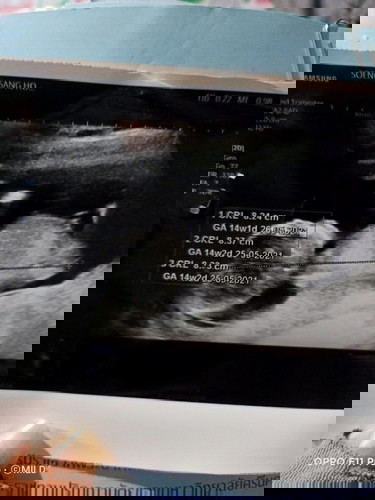

ตอนนี้25w แล้ว

26w2d ค่ะ กำหนด19 พ.ค. น้องผู้ชายค่ะ